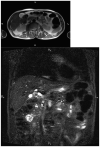

Figures